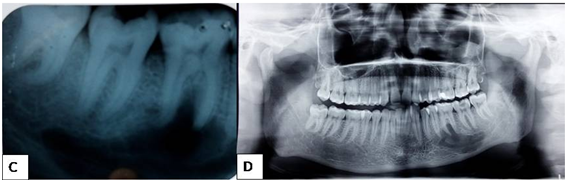

Figure 2 C- showing the extent of a well defined radiolucency in the IOPA of mandibular left back tooth region. D- showing the same on an OPG.

Even in the cases where the lesion is associated with roots of teeth, there is no increased mobility of the teeth or changes in their color. The present case too had normal appearing teeth associated with the lesion. Pulp vitality is not likely to be altered. However, due to traumatic force, cystic expansion may increase the root pressure resulting in a temporary reduction in the pulpal response to the electric test which holds good in our case too.9-15 Clinically, there are no soft tissue changes, pain or paresthesia. In the early phases, there is usually no bone expansion while in the later phase; there can be bone expansion. In our case there was no bone expansion.12 Periapical radiographs are ideal for early radiographic assessment but these radiographs fail to show the whole extent of the lesion. Panoramic radiography, computed tomography and magnetic resonance are more precise imaging modalities in the diagnosis of these cysts. In our case the cyst was an incidental finding in an IOPA the extent of which was found later by an OPG.8 Radiographically, these lesions appear as a well defined radiolucent defect with diameter in the range of range 1 to 10 cm as seen in our case.10 The cysts usually presents as scalloping pattern between the roots of the involved teeth which was seen in our case too where the cyst scalloped between the roots of 36 and 37.11 The structure of the mandible canal may in some cases be preserved and in other cases not. There is no resorption of the teeth roots. The lamina dura may or may not be involved.4 In our case, the lesion involved the mandibular canal, with loss of lamina dura but no root resorption. Histopathological examination reveals a thin band of vascular fibrous connective tissue lacking an epithelial lining. In our case also histopathological examination revealed bone tissue and extravasated RBCs without lining epithelium.13 Treatment is surgical operation which consists of evacuation of the content, cochleation of the cavity in order to stimulate bleeding in the cavity. The wound is then sutured. This is followed by the formation/creation and organisation of a clot, and healing by the formation of new bone.14 In our case also treatment consisted of bone curettage under local anesthesia and surgical closure of the wound. The patient will be monitored clinically and radiographically every 6 months to follow the progression of healing. Healing occurs about 6 to 24 months after bleeding and closure of the area. Prognosis is usually excellent with rare chance of recurrence15 (Figure 1-4)